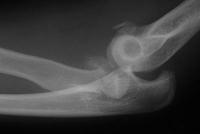

Radial head excision and coronoid soft tissue attachment reinsertion with bone anchors:

Click for larger image

Remodelling, heterotopic ossification and posttraumatic joint changes two years postoperative, but no instability: